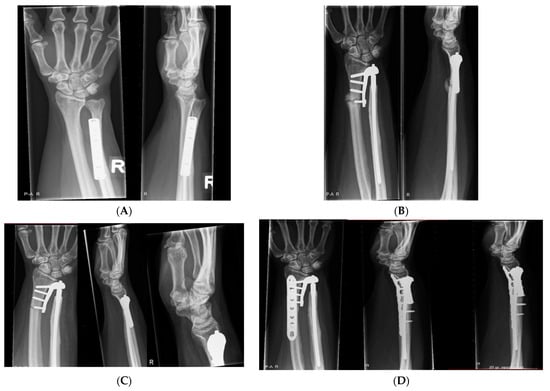

2.5. Radiographic Assessment

3.3. Radiological Evaluation

| Case | Radiological Evaluation | Combined Error | Translation Healthy | Translation Aptis | Δ Translation |

|---|---|---|---|---|---|

| 1 | Periprosthetic fracture; proximal screws | 11 | 1.5 | 0.5 | −1.0 |

| 2 | Lucency distal screw (37) | 6 | 2.8 | 0.6 | −2.2 |

| 3 | Heterotopic ossification (8) | 7 | 1.3 | 0.2 | −1.1 |

| 4 | No abnormalities | 5 | 2.8 | 0.5 | −2.3 |

| 5 | Heterotopic ossification (4) | 12 | 2.7 | 3.5 | 0.8 |

| 6 | - | 7 | 1.4 | 4.1 | 2.7 |

| 7 | Heterotopic ossification (5) + Lucency distal screw radius (13) | 14 | 2.1 | 0.3 | −1.9 |

| 8 | No abnormalities | 6 | 1.6 | 0.3 | −1.3 |

| 9 | Chip distal ulna (7) + Heterotopic ossification (24) | 13 | 1.8 | 0.3 | −1.5 |

| 10 | Dystrophic calcification (1.5) | 10 | 2.4 | 0.4 | −2.0 |

| 11 | Lucency distal screw (8) + heterotopic ossification (48) | 10 | 1.9 | 2.0 | 0.1 |

| 12 | Heterotopic ossification (57) | 9 | 1.7 | 0.3 | −1.4 |

| Average (SD) | 9 (3) | 2.0 (0.6) | 1.1 (1.3) | −0.9 (1.4) |